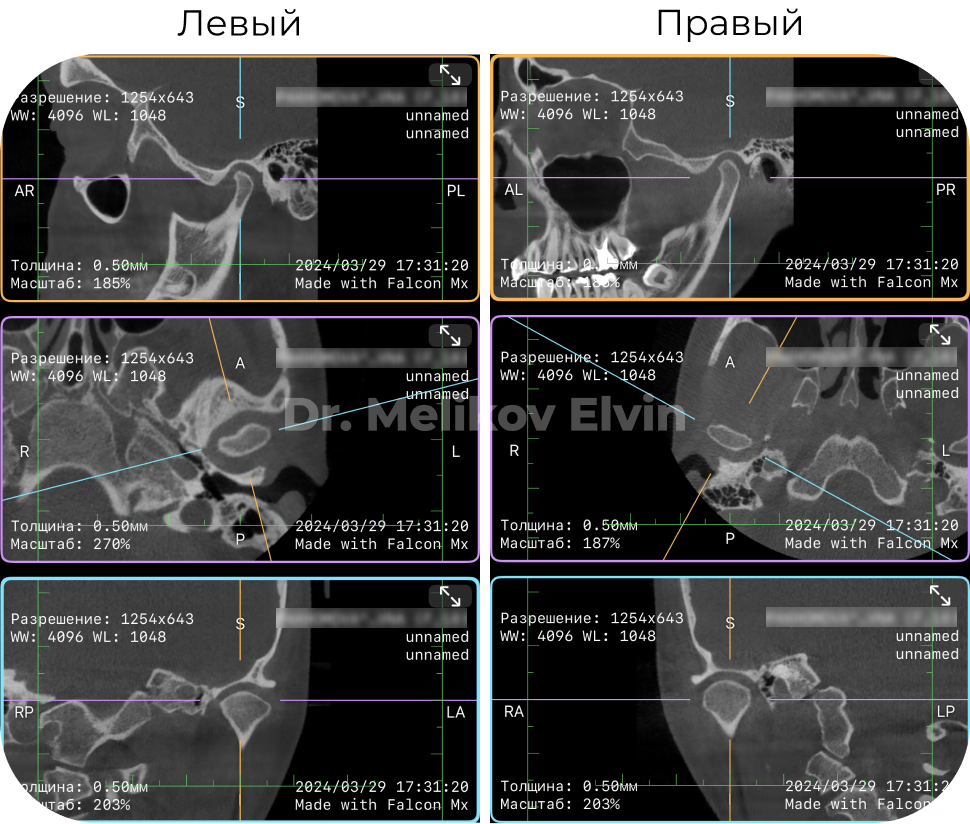

КТ ПОСЛЕ лечения